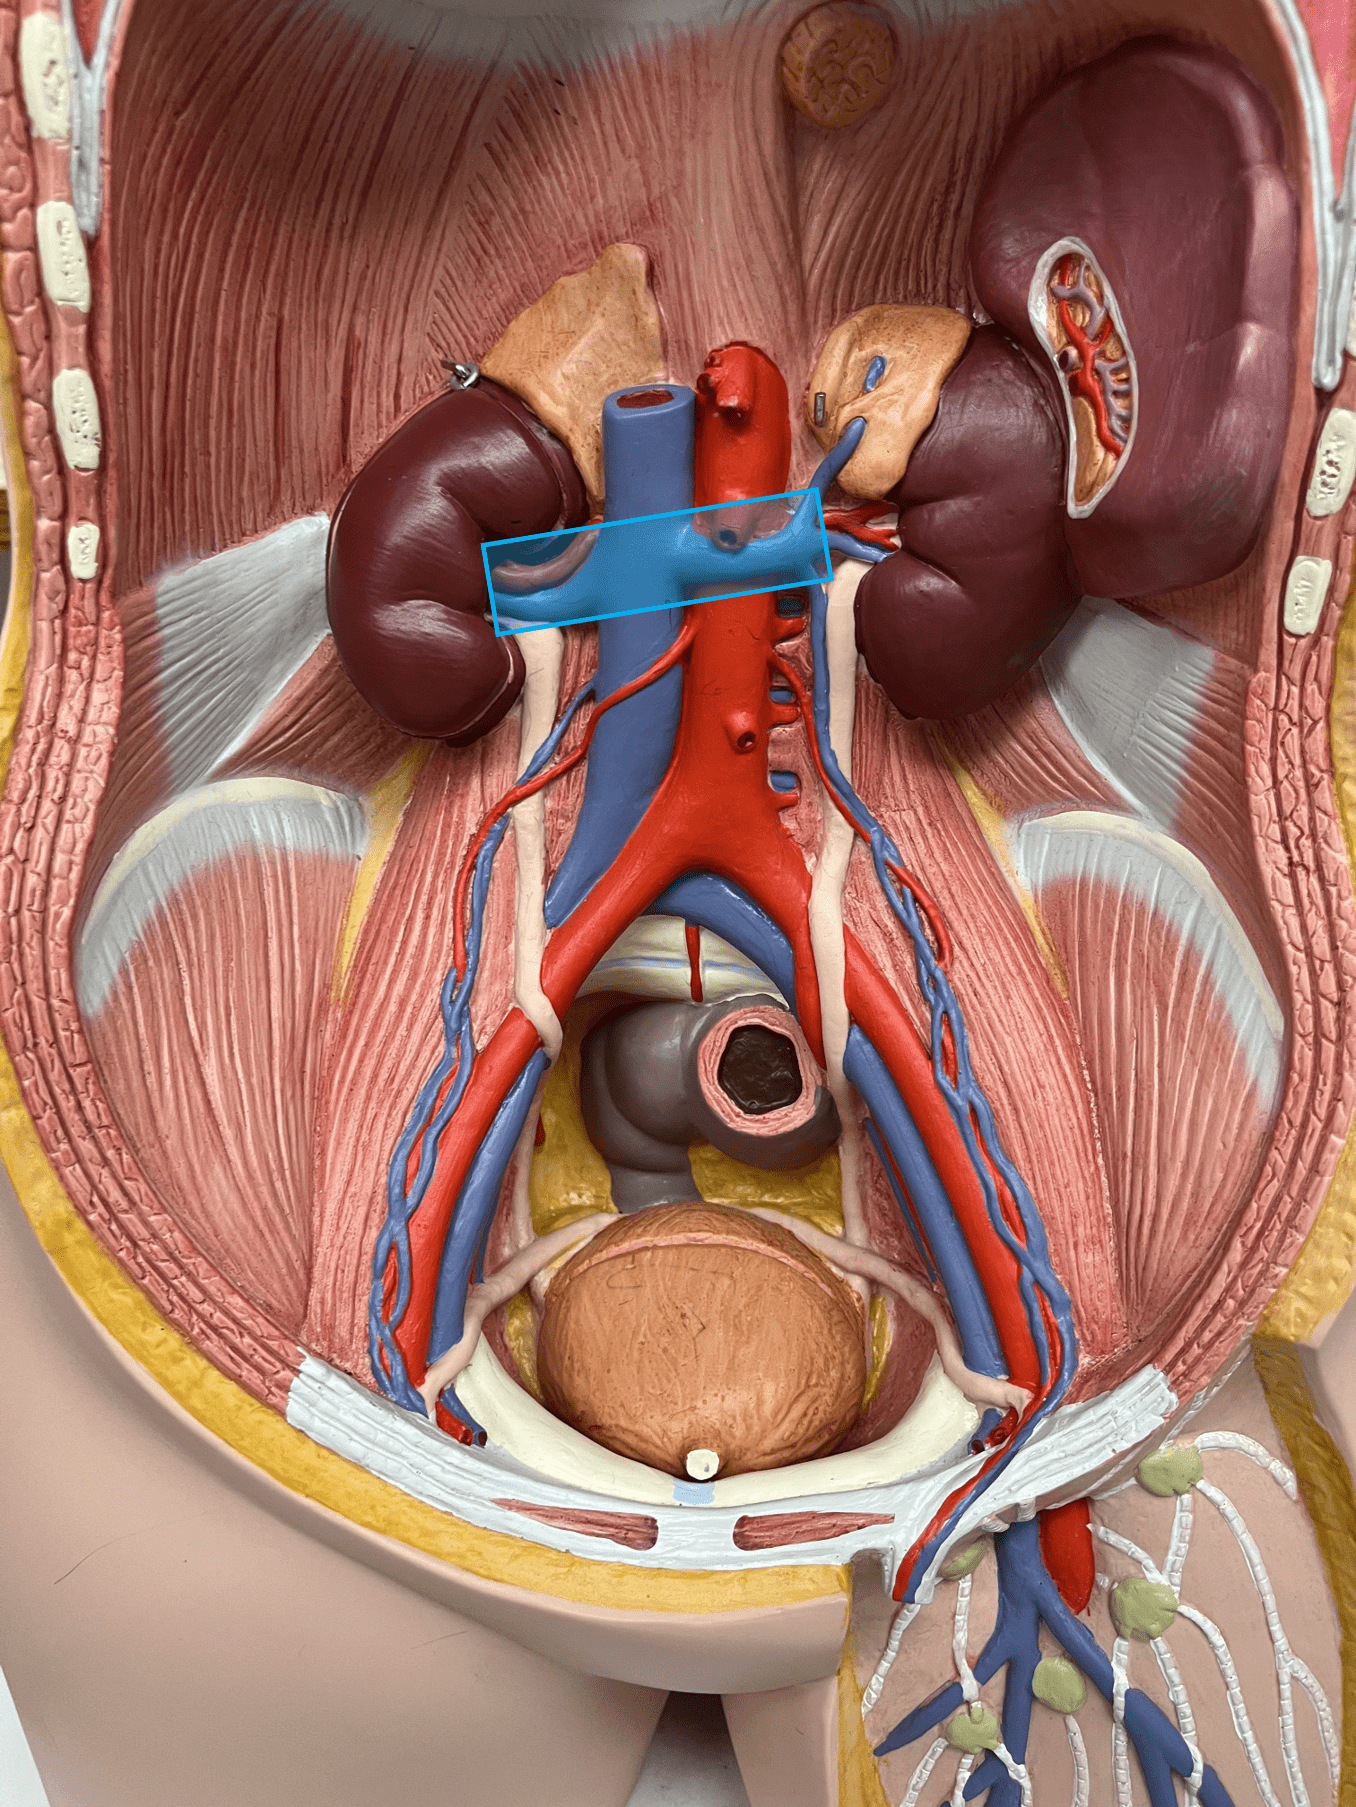

renal vein

• A vein of the abdomen.

• Drains the kidneys.

• Empties into the inferior vena cava.

• On the inferior vena cava, inferior to the hepatic veins and superior to the gonadal veins.

• Drains the kidneys.

• Empties into the inferior vena cava.

• On the inferior vena cava, inferior to the hepatic veins and superior to the gonadal veins.